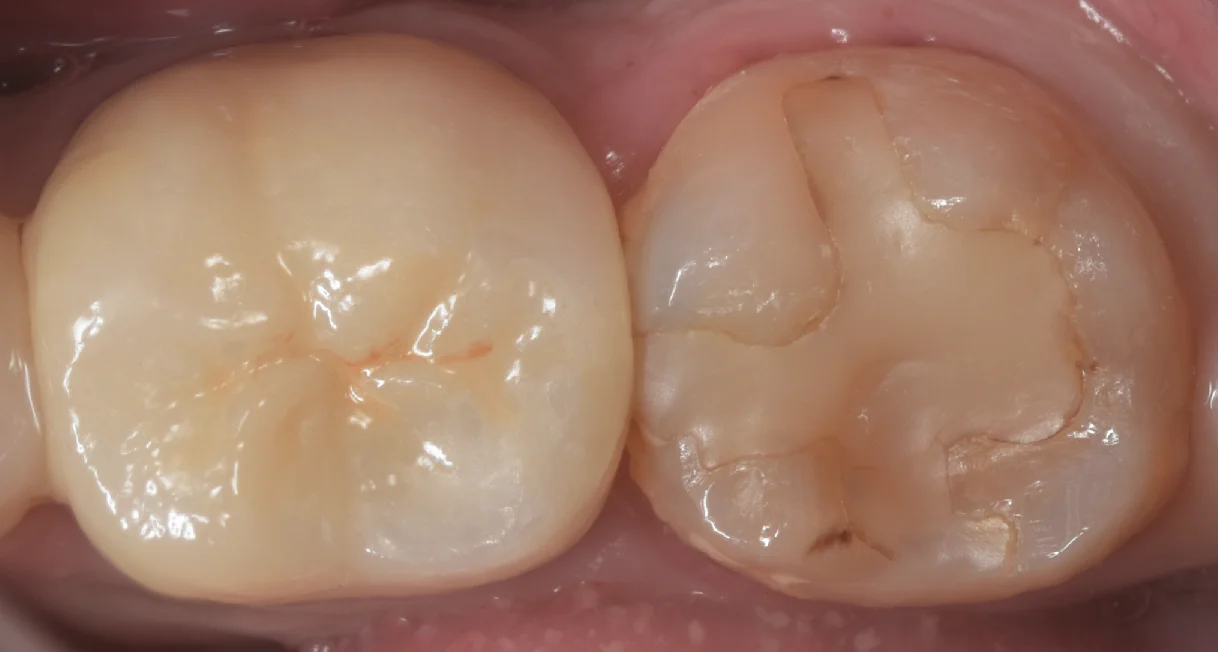

まずは術前からです。

画面右側が今回行う予定の古い白い詰め物です。

これ自体もそこそこ前のものらしいですが、目立った虫歯などはない状態でした。